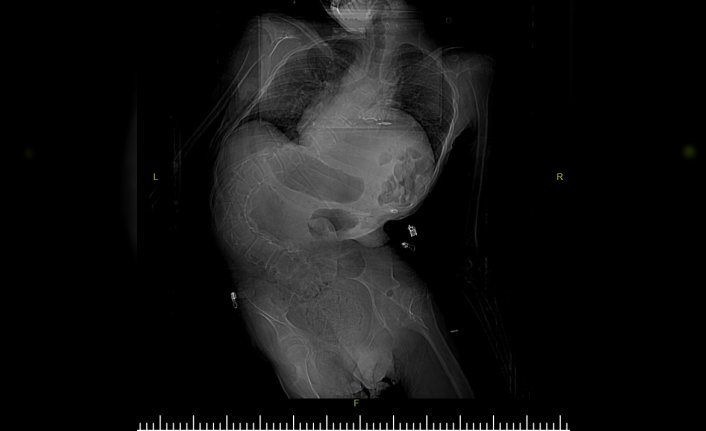

Samsun'da, skolyoz (omurga eğriliği) nedeniyle nefes almakta zorluk çeken ve kaburgaları kırılmaya başlayan serebral palsi hastası Enes Serçe, ameliyatla sağlığına kavuştu.

Serebral palsi nedeniyle gelişme geriliği olan ve skolyozu artan 17 yaşındaki Enes Serçe'nin nefes almakta güçlük çekmesi üzerine ailesi, Samsun Eğitim ve Araştırma Hastanesine başvurdu.

Hastanın, omurga eğriliğinde artma, solunum kapasitesinde azalma, iç organ baskılarının artması ve kaburgalarının kırılmaya başlaması nedeniyle ameliyat edildiğini anlatan Bozduman, "Hastamızı yaklaşık 5,5 saatlik ameliyatla başarıyla tedavi ettik. Yedi gündür hastamızı takip ediyorduk, artık taburcu edilebilir duruma geldi." dedi.